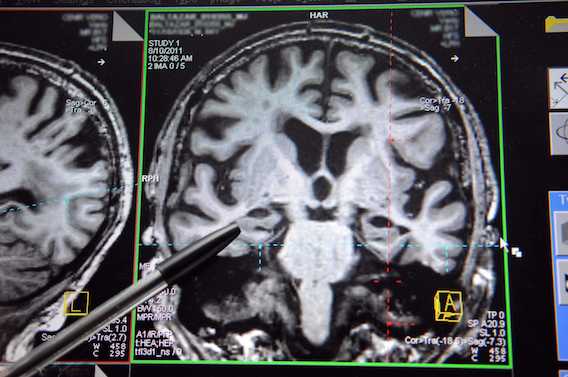

Donner son corps à la science permet aux médecins de progresser dans la compréhension des maladies. La dernière en date se situe sur le terrain de la neurologie. Des chercheurs de Montréal (Canada) pensent avoir découvert un chaînon manquant dans le développement de la maladie d’Alzheimer. Ils expliquent dans la revue Cell Stem Cell que les cerveaux des malades présentent une accumulation anormale d’acides gras.

L’équipe québécoise a autopsié les cerveaux de 9 personnes décédées de la maladie d’Alzheimer et de 5 personnes en bonne santé. L’accumulation d’acides gras était bien plus élevée chez les premiers. Une observation confirmée par des expériences sur des souris modifiées génétiquement pour développer la maladie. « Nos expériences suggèrent que ces dépôts anormaux pourraient être un déclencheur de la maladie », estime Karl Fernandes, qui a participé aux travaux.